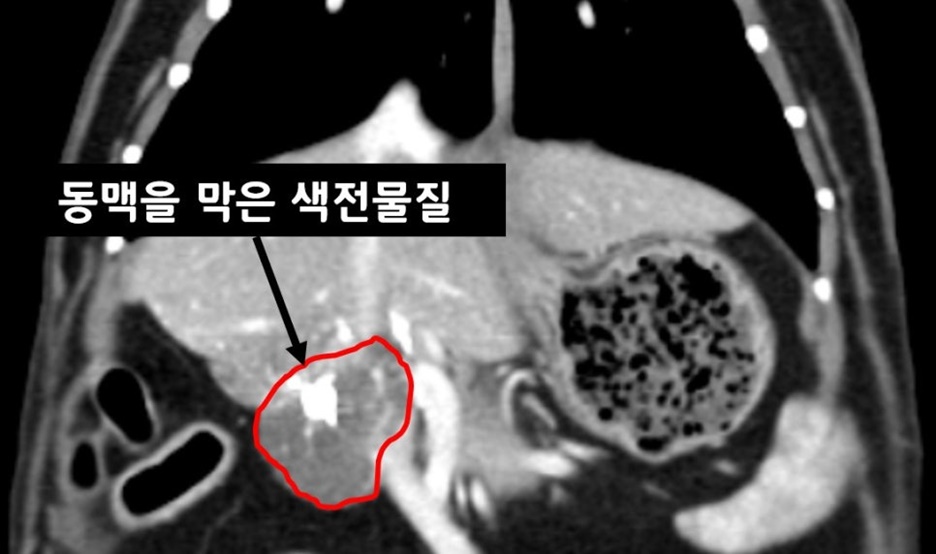

▲ 색전술 시술 6주 차

아이는 잘 회복했으며, 한 달 차에는 활력과 식욕도 모두 돌아왔습니다. 6주 차 CT 촬영에서는 종양의 대략 30%의 크기 감소를 확인했습니다. 종양의 영양 동맥(Feeding artery)을 막은 색전 물질이 확인됩니다.